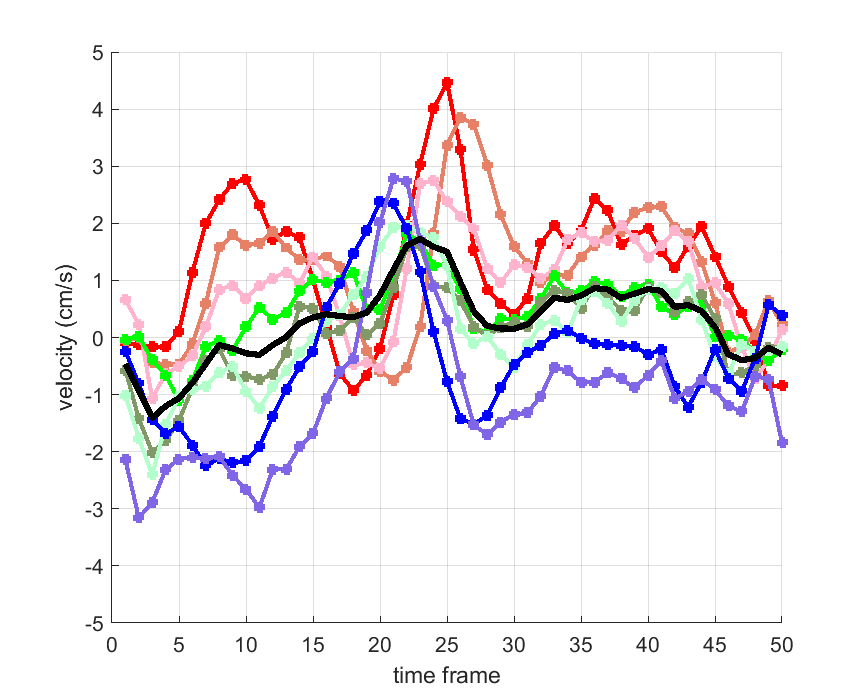

Time courses of the estimated translational component per subject, frame, slice and volume along the 3 velocity directions x, y and z are presented in Fig.6 - Fig.8.